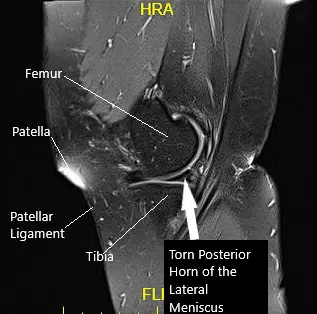

Sagittal MRI image of the left knee

MRI suggested lateral meniscus tear and trace joint effusion with possible recurrent patellar instability. We discussed treatment options and opted for surgical management. We discussed risks and benefits as well as complications including infection, bleeding, repeat surgery, injury to adjacent nerves. The patient agreed to go ahead with the procedure.